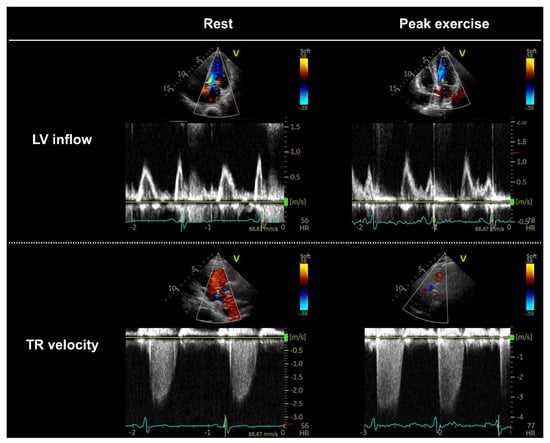

3.3. Stress Protocols, Image Acquisition, and Targeted Parameters

3.4. Interpretation of Test Results and Diagnosis of HFpEF